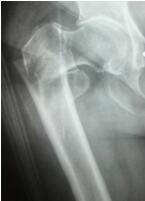

股骨頭(連接大腿和臀部的一個關節(jié))壞死全稱股骨頭缺血性壞死,是一種由股骨(即大腿骨)血供中斷或受損,引起骨細胞和骨髓成份死亡及隨后的修復,繼而導致骨頭結構改變,股骨頭塌陷,從而引發(fā)關節(jié)功能發(fā)生障礙的疾病。正常股骨頭壞死股骨頭因股骨頭壞死發(fā)病比較隱匿,且在不同病理階段會表現(xiàn)出不同的癥狀,所以,臨床上經(jīng)...

隨著我國人口老齡化加重,老年髖部骨折的病人也在逐年增加。據(jù)了解,高齡髖部骨折具有并發(fā)癥多、死亡率高的特點,國際上對于高齡老人髖部骨折治療方式首選手術治療,并且要求手術在傷后48小時內完成,越快越好。瀘州市中醫(yī)院通過多科協(xié)作,為髖部骨折的老年患者開啟快速就醫(yī)、快速檢查、快速手術、快速康復的綠色通道,成...